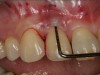

Clinical PPD is measured to the nearest millimeter by means of a graduated periodontal probe with a standardized tip diameter of approximately 0.4 mm to 0.5 mm. Several factors can influence the measurements made with periodontal probes, including: the thickness of the probe used5; the angulation and positioning of the probe depending on anatomic features, such as the contour of the tooth surface (Figure 1 through Figure 3)6; the graduation scale of the probe5; the pressure applied on the instrument during probing6; and the degree of inflammatory cell infiltration in the soft tissue and accompanying loss of collagen.7

Fig 1. Inaccurate probing angle wrongly indicates probing depth at 3 mm, which does not correspond to the radiographic finding shown in Fig 2.

Figure 1

Fig 3. Correct angulation of the probe demonstrates 6-mm probing depth.

Figure 3